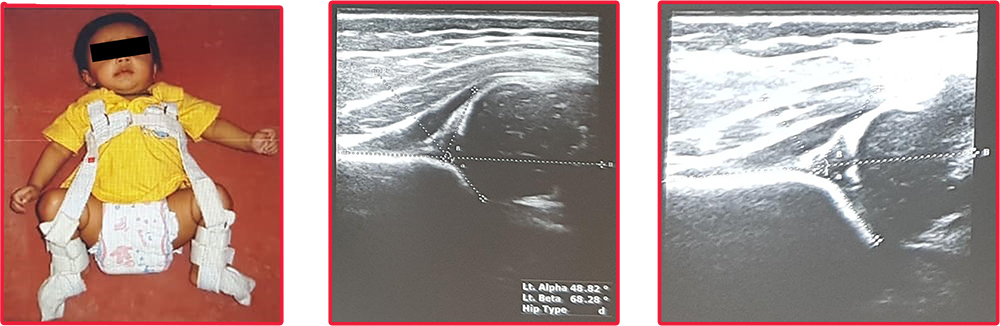

• Ultrasound (Under 6 Months): Preferred for young infants because much of the hip joint is still made of cartilage, which does not show up well on X-rays.

0–6 Months Pavlik Harness A soft brace that holds the legs in a "frog" position (flexed and out). It allows the hip to deepen naturally over 6–12 weeks.